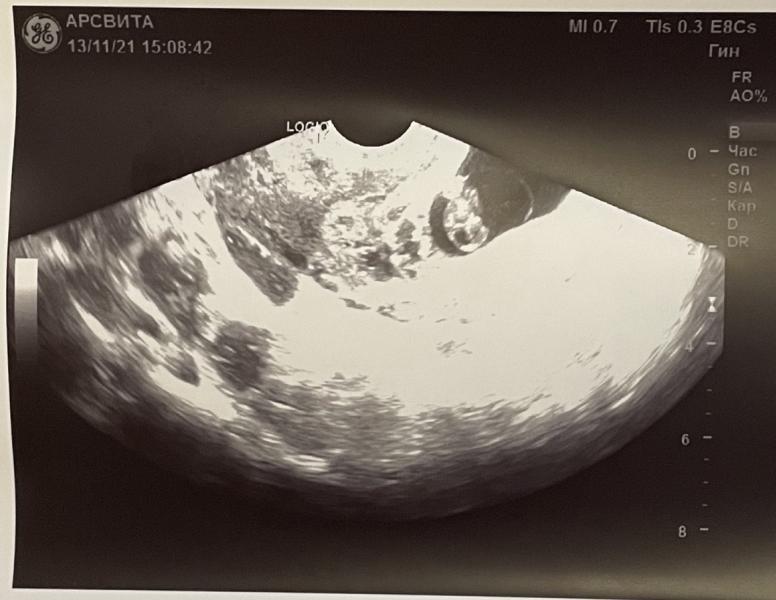

13 ноября 7 недель 4 дня, сходила на узи.

ктр до 14мм, желточный мешочек до 5мм, чсс 120уд/мин.

Гематома на месте, киста на месте, по узи 8 недель, но не в этом суть!

В головном конце эмбриона (в шее) обнаружено анэхогенное включение!… что это вообще может быть?.. начиталась ужасов, но это всё не точно же..((